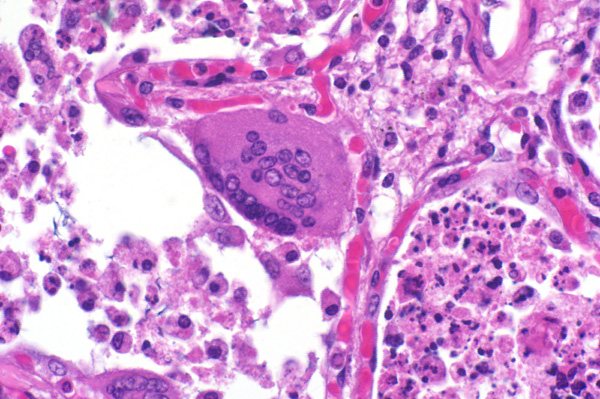

There are many syncytial cells that contain up to 20 nuclei. The surrounding interstitium (circled) is expanded by fibrin and edema, degenerate neutrophils, and eosinophilic cellular and karyorrhectic debris.